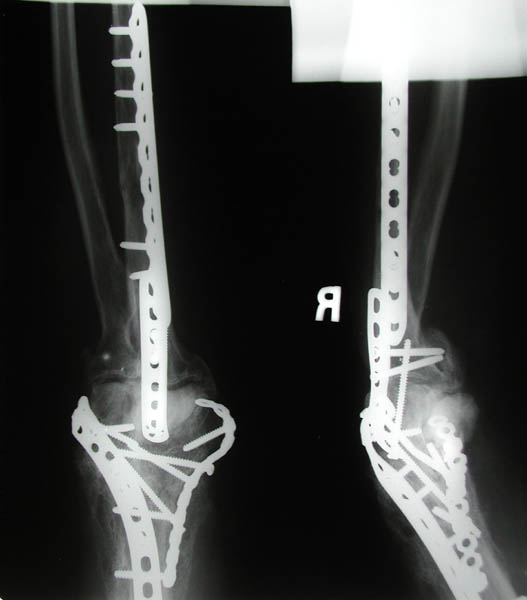

Front and side views of Marla's right elbow before her April 22nd elbow replacement surgery. The screws and plates were emplaced during the first re-construction post-trauma in December 2002. The entire infrastructure was surrounded by and interwoven with excess bone build-up, a common side effect of joint trauma coincident with head trauma. This excess bone had to be removed during her elbow replacement surgery.